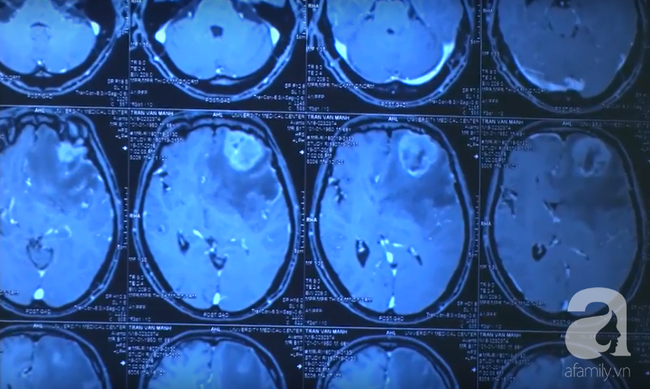

Thăm khám và thực hiện chụp cộng hưởng từ sọ não, các bác sĩ chẩn đoán bệnh nhân có tổn thương choáng chỗ vùng vỏ não vận động có thể do u hoặc nang ký sinh trùng trong não.

Hình ảnh ký sinh trùng qua ảnh chụp CT não.